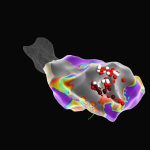

- Αφαίρεση Κοιλιακής Ταχυκαρδίας με Χρήση Τρισδιάστατης Χαρτογράφησηςby Ioannis KoulouridisΠραγματοποιήσαμε με επιτυχία αφαίρεση εμμένουσας μονομορφικής κοιλιακής ταχυκαρδίας (VT) σε ασθενή με ισχαιμική μυοκαρδιοπάθεια και επανειλημμένα shocks από εμφυτεύσιμο απινιδωτή (ICD), παρά τη χρήση αντιαρρυθμικών φαρμάκων. Χρησιμοποιήθηκε υψηλής ανάλυσης 3D ηλεκτροανατομική χαρτογράφηση, με στόχο τη λεπτομερή καταγραφή των ουλωτικών περιοχών και των παθολογικών ηλεκτρογραμμάτων. 🔸 Η χαρτογράφηση τάσης (Voltage Map, πρώτη εικόνα) ανέδειξε εκτεταμένη ουλή[…]